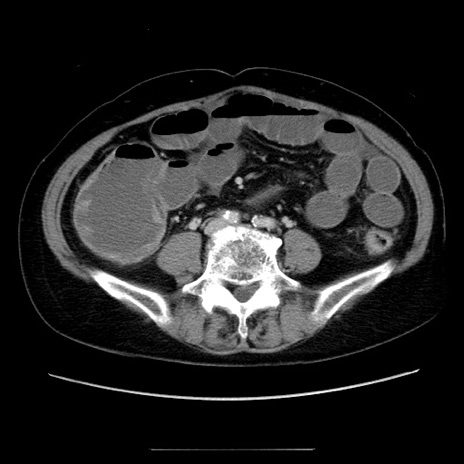

症例5(横断像)

【症例】70歳代女性

【主訴】お腹が張る

【現病歴】1週間くらい前から腹部膨満の自覚あり。昨日夜から増悪したため、本日救急外来受診。

【身体所見】意識清明、BT 36.5℃、BP 165/106mmHg、HR 80bpm、SpO2 98%、腹部:膨満、軟、自発痛・圧痛なし、触診にて不快感あり、腸蠕動音:減弱

【データ】WBC 12600、CRP 1.04